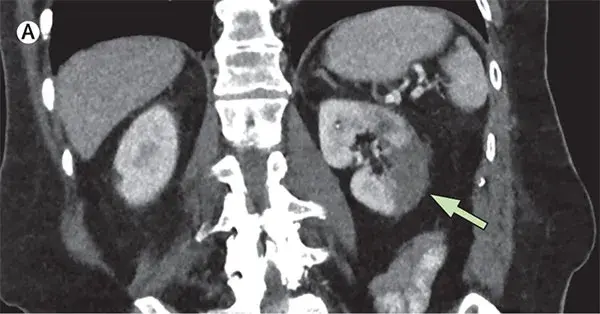

Mudança dinâmica do tamanho renal?

Mudança dinâmica do tamanho renal?Um homem de 39 anos foi internado no hospital com história dia com dor no flanco esquerdo e tontura há um dia. Paciente tinha antecedentes de diabetes mal controlado e nefrolitíase obstrutiva é esquerda. Após avaliação inicial a TC do abdome mostrou aumento do tamanho do rim esquerdo devido gás no parênquima renal, espaço perirrenal